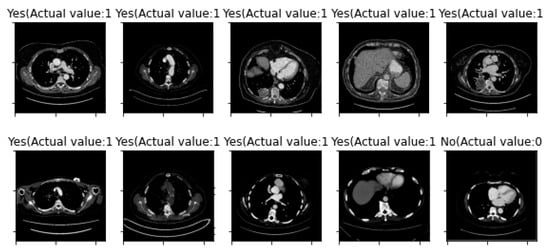

3. Results

| First Run: | Second Run: | ||

| Training Sample Error Rate | 5% | Training Sample Error Rate | 5% |

| Testing Sample Error Rate | 14.586% | Testing Sample Error Rate | 8.091% |

| Accuracy | 85.414% | Accuracy | 91.909% |